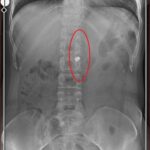

Tedavi gördüğü hastanede bir sürü operasyon geçiren ve isabet eden 7 mermiden 6’sı bulundukları yerlerden çıkarılamadıkları için vücudunda 6 mermi ile yaşayan Fatma O. ise iki sene sonra dehşeti yaşadığı evin önüne gidip yaşadıklarını unutup yeniden hayata tutunacağını söyledi. Evlilik için gün sayan Fatma O., kendisine hediye edilen gelinliği görünce gözyaşlarını tutamadı. 2 sene önce yaşadığı kabus dolu 23 günü anlatan genç kadın, İlyas Sarıkaya’nın ceza aldığını görmeden huzura eremeyeceğini dile getirdi.

Hastane sürecinden de bahseden genç kadın, “Apayrı bir süreçti. Baştan hiçbir doktor bana dokunmak istemedi olayın üzerinden 23 gün geçtiği için zaten mermilerin hala 6’sı vücudumda sadece teki çıkarıldı. Bacağımda kırıklar vardı. Yaşadığım olayı hala atlatmış değilim çok ağır ilaçlar kullanıyorum dolayısıyla çalışamıyorum. Uzun süre ayakta kalamıyorum karşıdan bir insan geliyor, geçende biri cebinde çakmak çıkarmaya çalışıyormuş ben silah çıkarıyor sandım tabureyle saldırdım. Allah’tan anlayışlı birisiymiş. Havai fişekler patlayınca ben çıldırıyorum bu travmaları halen yaşıyorum. Bu süreçte en büyük desteği kızımdan gördüm. Kızım benim evladım. Bir de aslanım var. Kocamın ismi Aslan her şeyi onlara borçluyum” diye konuştu.